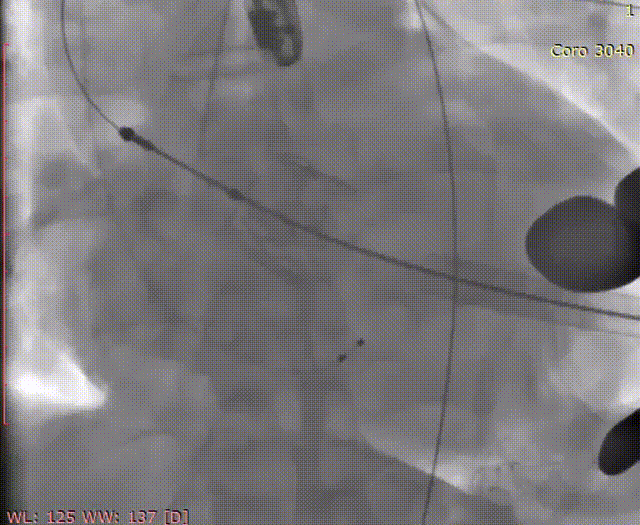

三个定位件入窦

转2下降瓣架

确定瓣膜位置

植入经心尖J-Valve29mm瓣膜,最终通过造影和即刻超声评估,人工瓣膜释放位置和形态满意,无反流。患者一般情况良好,手术顺利结束。